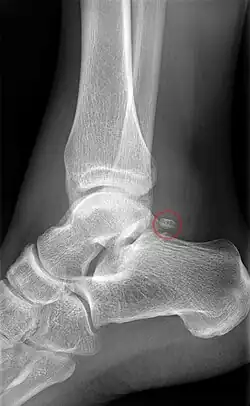

Het os trigonum is vaak een incidentele bevinding bij radiologisch onderzoek.[3] Op röntgenfoto's wordt het soms onterecht aangemerkt als afwijkend, losliggend botdeel of als fractuur.[9] Met name verwarring met een Shepherd-fractuur, een zeldzame fractuur van de laterale tuberkel van de processus posterior van het sprongbeen, komt veelvuldig voor.[2] Zelfs Shepherd maakte die vergissing.[10] In de verdere differentiaaldiagnose behoren een Cedell-fractuur (een fractuur van de mediale tuberkel van de processus posterior van de talus) en pseudartrose. Met behulp van CT en MRI kunnen ook het omliggende bot- en steunweefsel worden geëvalueerd om de klinische betekenis van het additionele botje vast te stellen.[3]